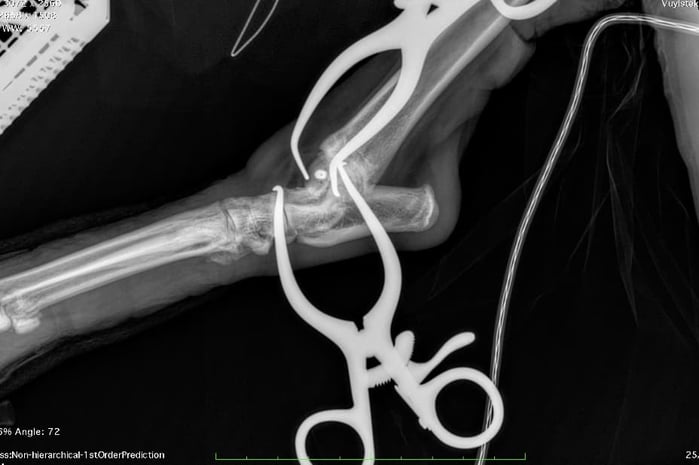

Instead, Mark and the team opted for an innovative solution: a headless compression screw (HCS), commonly used in human orthopaedic surgery for peri-articular fractures. The HCS generates compression along the fracture line thanks to its differential thread pitch, while its headless design allows full burial within the bone—eliminating the risk of joint interference.

The fracture’s small size, delicate location, and proximity to the joint meant precision was critical. To ensure accurate screw placement, Mark performed the surgery under real-time intra-operative imaging — a technique he has refined over more than a decade. Using continuous X-ray guidance allowed confirmation of ideal screw trajectory and depth, avoiding both joint violation and inadequate fracture engagement.

Continuous intra-operative x-ray was used to guide placement of screw